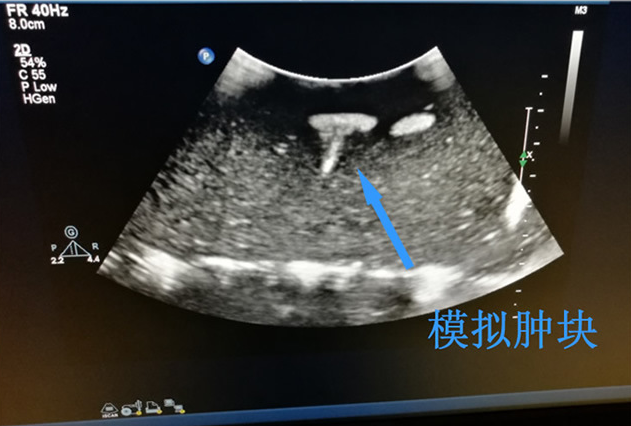

頸部影像的組織清晰顯示內(nèi)部病變的結(jié)構(gòu)和位置,凸出的表面輪廓類似人體皮膚;

可用真實(shí)B超超聲影像,滿足不同的教學(xué)考核需要。